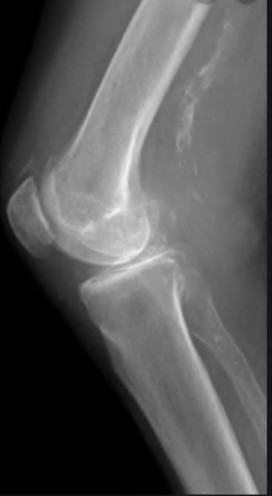

A 65-year-old woman with painful knee arthritis and the deformity seen in Figure A, is scheduled to undergo a total knee arthroplasty. All the following are risk factors for a post-operative peroneal palsy EXCEPT:

The clinical presentation is consistent with end-stage arthritis in a valgus knee. All of the factors listed are risk factors for peroneal nerve palsy EXCEPT female gender, which is not a risk factor.

Peroneal nerve palsy is a potential serious complication of TKA in patients with a pre-operative valgus knee deformity. Peroneal nerve palsy is likely caused by lengthening of the lateral aspect of the knee and subsequent traction on the peroneal nerve. It is generally recommended that patients be evaluated

carefully for symptoms postoperatively. If peroneal nerve palsy symptoms are discovered, the knee should be flexed to relax the tension that is effectively being placed on the nerve. If peri-operative nerve exploration or decompression is undertaken, the posterior border of the biceps-femoris tendon is the proper site of identification.

Idusuyi et al. published a retrospective review of 32 postoperative peroneal nerve palsies in thirty patients in which they identified possible risk factors. Prior proximal tibial osteotomy, lumbar laminectomy (thought to be a “double-crush” phenomenon), and preoperative valgus alignment of 12 degrees or more were all identified as risk factors. Other concerns included epidural anesthesia for postop pain control, preoperative flexion contractures and tourniquette time greater than 120 minutes also increased concern.

Favorito et al reviewed valgus total knee arthroplasty and reported that the most common complications of patients with a valgus deformity include: tibiofemoral instability (2% to 70%), recurrent valgus deformity (4% to 38%), postoperative motion deficits requiring manipulation (1% to 20%), wound problems (4% to 13%), patellar stress fracture or osteonecrosis (1% to 12%), patellar tracking problems (2% to 10%), and peroneal nerve palsy (3% to 4%).

Figure A demonstrates and AP radiograph of the knee showing end-stage arthritis with severe lateral compartment narrowing.